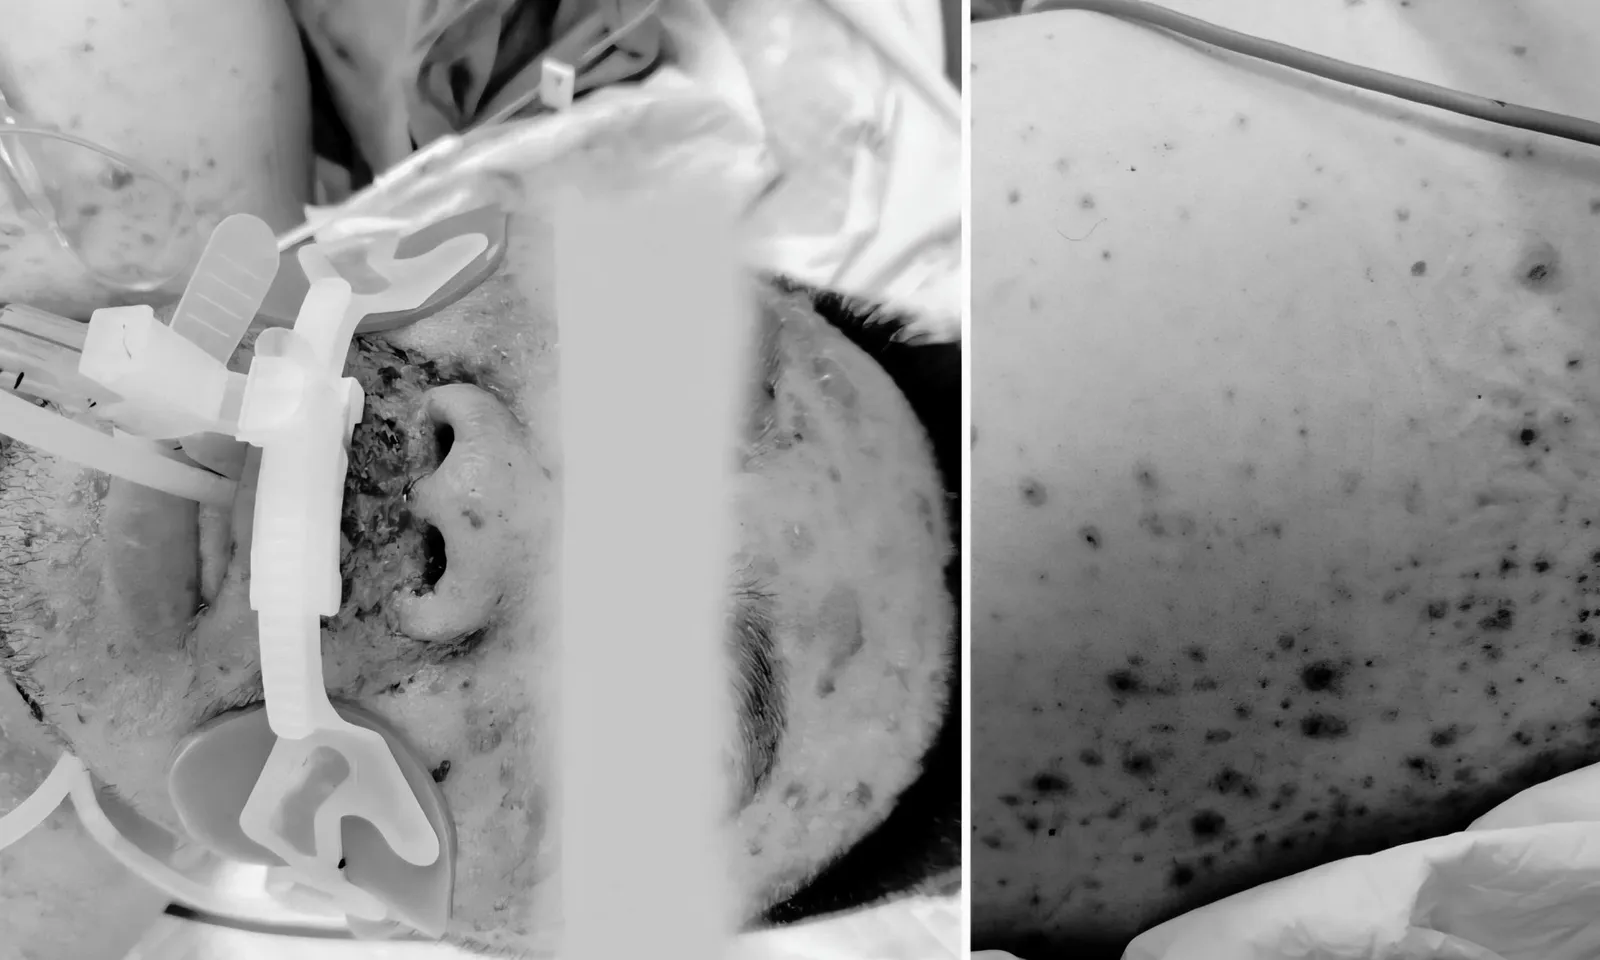

Bệnh nhân nhập viện trong tình trạng kích thích, vật vã, sốc, suy hô hấp, huyết áp tụt, thăm khám có nhiều ban thâm tím hoại tử khắp mặt, ngực, hai tay, kèm đi ngoài phân lỏng nước nhiều lần.

Sau đó, người bệnh xuất hiện mệt nhiều, khó thở, đau đầu, buồn nôn, xuất hiện các ban xuất huyết và nhanh chóng rơi vào tình trạng nguy kịch.

Bệnh nhân được chẩn đoán sốc nhiễm khuẩn, suy đa tạng do nhiễm liên cầu heo. Ngay khi nhập viện, bệnh nhân được các bác sĩ cấp cứu tích cực và qua cơn nguy kịch nhưng tiên lượng còn dè dặt.